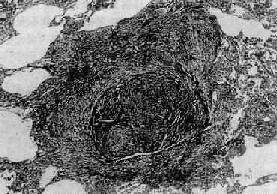

图9-22 矽肺 矽结节,由呈旋涡状排列的已发生玻璃样变的胶原纤维构成

三、职业性肺疾病在职业活动、特别是生产过程中,因长期吸入有害粉尘,引起以肺广泛纤维化为主要病变的疾病,统称尘肺(pneumoconiosis)。尘肺是我国一种法定职业病。属职业性尘肺的病种较多,按粉尘的化学性质可将其分为无机尘肺和有机尘肺两大类。无机尘肺中常见的有硅肺、煤工尘肺、石棉肺等。有机尘肺是因吸入各种有机尘埃,最常见的是由霉菌的代谢产物或动物性蛋白质引起的尘肺,如农民肺、蔗尘肺、蘑菇肺、麦芽肺和饲禽者肺等。尘肺对健康危害极大,关键在于预防。改革不合理的生产过程,建立粉尘监测制度,切实落实综合防尘措施。不接触粉尘或减少吸入粉尘的机会,对于粉尘作业工人定期体检,做到早期检查、早期诊断,对已确诊为尘肺患者及早调离粉尘作业,并进行必要的治疗,完全可以控制和减少尘肺的发病率。 (一)矽肺 矽肺(silicosis)是在生产环境中长期吸入大量含游离二氧化硅(SiO2)粉尘微粒所引起的以肺纤维化为主要病变的全身性疾病。游离二氧化硅主要存在于石英中,石英成分中SiO2占97%~99%。约有70%的矿石中均含有较多的SiO2。长期从事开矿、采石作业、坑道作业以及在石英粉厂、玻璃厂、耐火材料厂、陶瓷厂和搪瓷厂生产作业的工人易患本病。矽肺是危害最严重的一种职业病,其特点是发展缓慢,即使在脱离矽尘作业后,病变仍然继续缓慢发展。患者多在接触矽尘10~15年后才发病。若因吸入高浓度、高游离二氧化硅含量的矽尘,经1~2年后发病者,称速发型矽肺。矽肺的早期即有肺功能损害,但因肺的代偿能力很强,患者往往无症状,随着病变的发展,尤其是合并肺结核和肺心病时,则逐渐出现不同程度的呼吸和心功能障碍。 【病因和发病机制】 游离二氧化硅是矽肺的致病因子。矽肺的发生、发展与矽尘中游离二氧化硅的含量,生产环境中矽尘的浓度、分散度,从事矽尘作业的工龄及机体防御功能等因素有关。矽尘粒子愈小,分散度愈度,在空气中的沉降速度愈慢,被吸入的机会就愈多,致病作用亦愈强。一般来说,大于5μm的矽尘往往被阻留在上呼吸道,并可被呼吸道的防御装置清除。小于5μm的矽尘才能被吸入肺泡,并进入肺泡间隔,引起病变。尤以1~2μm的矽尘微粒引起的病变最为严重。 吸入肺泡内的矽尘微粒被肺巨噬细胞吞噬,沿肺淋巴流经细支气管周围、小血管周围、小叶间隔和胸膜再到达肺门淋巴结。当淋巴道阻塞后,矽尘沉积于肺间质内引起矽肺病变。若局部沉积的矽尘量多,引起肺巨噬细胞局灶性聚积,可导致矽结节形成;若矽尘散在分布,则引起弥漫性肺间质纤维化。矽肺的发病机制尚未完全阐明。一般认为,矽尘被肺巨噬细胞吞噬后,在游离二氧化硅的毒性作用下,巨噬细胞大量死亡崩解或发生功能和生物学行为改变,释放出一些致纤维化因子、包括巨噬细胞生长因子(MDGF),白细胞介素Ⅰ(IL-1)和纤维连结蛋白(FN)等,促进成纤维细胞增生和胶原形成,导致纤维化。至于巨噬细胞死亡的原因,主要是由于矽尘被巨噬细胞吞噬后,存在于次级溶酶体中,矽尘表层中的SiO2逐渐与水聚合成硅酸(系一种强的成氢键化合物),其羟基基团与溶酶体膜脂蛋白结构上的受氢原子(氧、氮或硫)间形成氢键,改变了溶酶体膜的脂质分子构型,从而破坏了膜的稳定性或完整性。溶酶体膜通透性增高或破裂,其中所含的大量水解酶溢出到细胞内,导致巨噬细胞自溶崩解。巨噬细胞死亡崩解后,释出的矽尘又被其它巨噬细胞吞噬,如此反复进行,使病变不断发展、加重。这也可解释何以患者脱离矽尘作业后肺部病变仍然会继续发展的缘由。 随着免疫学的发展,大量关于矽肺免疫的研究表明,在矽肺发生、发展过程中,有免疫因素参与。根据对矽结节玻璃样变组织的生化分析,其中球蛋白含量明显高于胶原含量,而有别于一般的玻璃样变组织的成分。动物实验证明,矽肺病变的纤维化程度与浆细胞反应强度呈正相关,提示矽肺的纤维化与抗原抗体反应有关。用荧光免疫组织化学方法观察矽结节,发现在胶原纤维及其间隙中有大量γ-球蛋白沉积,主要是IgG和IgM。如将尸检取得的矽结节玻璃样变组织制成匀浆,给家兔注射后,能产生抗人γ-球蛋白抗体。有人认为,浆细胞产生的免疫球蛋白通过形成抗原抗体复合物参与矽肺的发病。对矽肺患者作体液免疫测定发现,血清中IgG和IgM浓度增高,抗肺自身抗体、抗核抗体和类风湿因子检出率也较高。但关于矽肺免疫的抗原物质目前还未提取出来,多认为有3种可能性:①矽尘作为半抗原与机体的蛋白质结合构成复合抗原;②矽尘表面吸附的γ-球蛋白转化为自身抗原;③矽尘导致巨噬细胞死亡崩解后释放自身抗原。现已有很多证据表明,巨噬细胞死亡崩解后释放抗原的可能性最大。总之,矽肺的病因是明确的,发病机制极为复杂,在发病过程中可能有多种因素参与,它们互相影响、互为因果,共同促进矽肺的发生和发展。 【病理变化】 矽肺的基本病变是肺组织内矽结节形成和弥漫性间质纤维化。矽结节是矽肺的特征性病变,结节境界清楚,直径2~5mm,呈圆形或椭圆形,灰白色,质硬,触之有砂样感。随着病变的发展,结节可融合成团块状,在团块的中央,由于缺血、缺氧而发生坏死、液化,形成矽肺性空洞(silicotic cavity)。矽结节的形成过程大致分为三个阶段:①细胞性结节,由吞噬矽尘的巨噬结胞局灶性聚积而成,巨噬细胞间有网状纤维,这是早期的矽结节;②纤维性结节,由纤维母细胞、纤维细胞和胶原纤维构成;③玻璃样结节,玻璃样变从结节中央开始,逐渐向周围发展,往往在发生玻璃样变的结节周围又有新的纤维组织包绕。镜下,典型的矽结节是由呈同心圆状或旋涡状排列的、已发生玻璃样变的胶原纤维构成(图9-22)。结节中央往往可见内膜增厚的血管。用偏光显微镜观察,可以发现沉积在矽结节和肺组织内呈双屈光性的矽尘微粒。除矽结节外,肺内还有不同程度的弥漫性间质纤维化(图9-23),范围可达全肺2/3以上。此外,胸膜也因纤维组织弥漫增生而广泛增厚,在胸壁上也可形成胸膜胼胝,甚至可厚达1~2cm。肺门淋巴结内也有矽结节形成和弥漫性纤维化及钙化,淋巴结因而肿大、变硬。